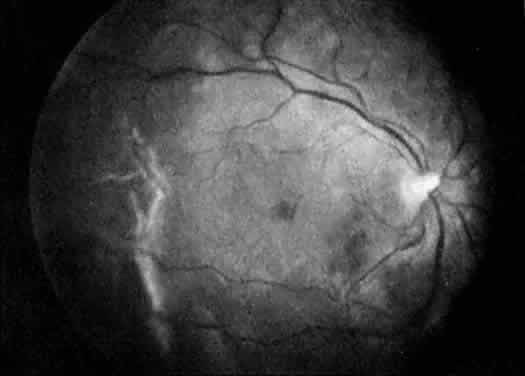

The ocular manifestations of antiphospholipid antibodies include retinal venous and arterial occlusions, amaurosis fugax, diplopia, and visual field loss.34,35 Extensive vasoocclusion, neovascularization, and vitreous hemorrhage may occur (Fig. 3). Treatment consists of photocoagulation for the neovascularization and systemic anticoagulation and immunosuppression. Vitrectomy may be required for vitreous hemorrhage. The role of systemic treatment of lupus anticoagulant in the management of ocular disease is unclear. Some investigators suggest that systemic anticoagulation be started promptly.36 The optimal duration of anticoagulation and whether antiplatelet therapy should be used are not known however. The optimal use of corticosteroids or other immunosuppressive drugs such as cyclophosphamide and azathioprine also is unknown. Two reports have found an association with the antiphospholipid syndrome and some additional retinal conditions. One report also has associated the primary antiphospholipid syndrome with central serous chorioretinopathy.37 In addition, lupus anticoagulant positivity could represent an additional risk factor for diabetic retinopathy according to a recent report.38